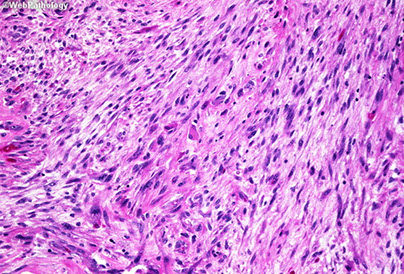

Micro: fascicular monomorphic serpentine spindle cells c large vascular spaces with geographic necrosis c palisading around edges

- lots o mits

MPNST